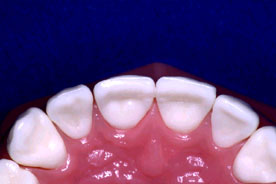

En este paciente, el incisivo superior presentaba una fractura traumática y fue tratado endodónticamente. Nótese el gran espacio radicular debido al diente inmaduro, ápice abierto.

Caso Clínico: Bill Bartel, DDS

El diente fue tratado endodónticamente con apexificación utilizando hidróxido de calcio y luego se rellenó con gutapercha. Observe el gran espacio del canal y la delgada estructura interior del diente.

El diente fue restaurado como se ha descrito anteriormente, se grabó el canal radicular, se colocó adhesivo y un composite híbrido dual. Para este caso se utilizaron dos piezas de Ribbond de 3 mm que se colocaron en la resina usando un instrumento para endodoncia de Ribbond.

2 piezas de Ribbond de 3mm

colocadas dentro del canal

Debido a que el paciente era un joven adolescente la restauración final fue una Clase IV de composite. En la radiografía se ve como la fibra Ribbond se ha unido al composite.